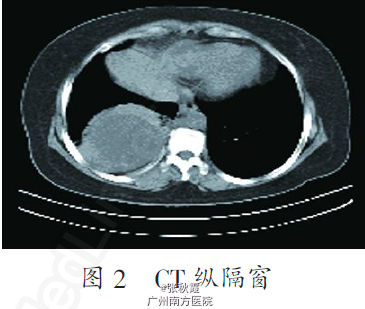

辅查:CT 表现(图1,2):右肺下叶见直径约8.0 cm 的球形病灶,边缘稍毛糙,未见明显分叶,壁厚薄欠均,内壁较光整,内见液性密度影,CT值约15.0 Hu,邻近胸膜增厚,纵隔内未见明显肿大淋巴结影,两侧胸腔未见积液。

诊断:右肺下叶占位,疑诊肺癌,肺脓肿不排除。 手术所见:剖胸探查右下肺见8 cm×7 cm×7 cm 大小包块,与胸壁、膈肌粘连,钝性分离粘连,行右下肺叶切除术。病理报告:右下肺囊肿伴肺组织脓肿形成。